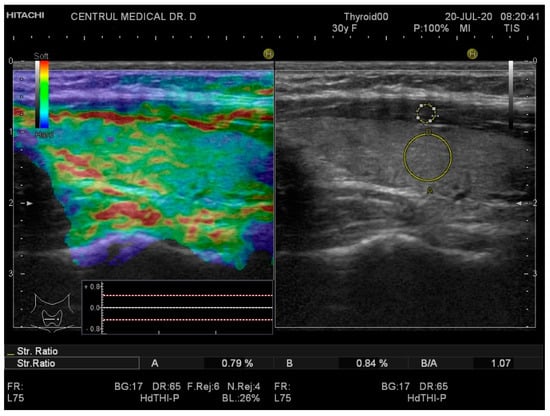

Real-time elastography was performed after conventional US during the same visit. The stiffness measurements were collected in the same session as the grey-scale US evaluation. The probe was placed perpendicularly to the skin and repetitive, light compression was applied avoiding lateral movement. All images were obtained in the longitudinal plane. A blue-green-red color map was displayed with blue indicating no strain (high stiffness), green indicating intermediate stiffness and red representing soft tissue. In order to calculate the strain ratio (SR), two regions of interest (ROI) were placed consequently. The first one, ROI A, was the thyroid tissue while the second one, ROI B, was the sternocleidomastoid muscle in front of the ipsilateral thyroid parenchyma. Figure 1 and Figure 2 below illustrate the SE image and calculation of the SR in normal thyroid tissue and, respectively, in a patient with CAT. Five consecutive measurements were made for each lobe and the mean value was considered in the final evaluation. The SR was calculated and displayed automatically for each lobe.

Figure 1. Strain elastography (left) and grey-scale ultrasound (US) (right) of a healthy patient—left thyroid lobe. The yellow circle A is the local region of interest (ROI) on the thyroid tissue; the yellow circle B is the local ROI on the sternocleidomastoid muscle adjacent to the thyroid. Strain ratio (SR) = 1.07.